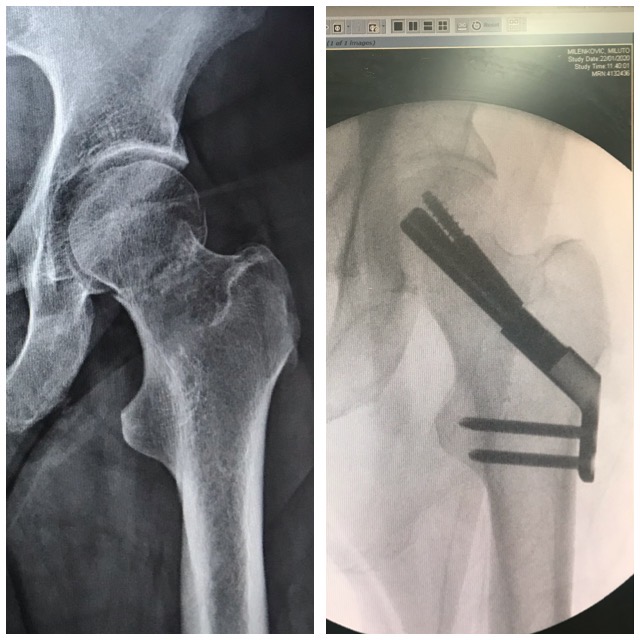

Lonkkamurtuma

Ennen – Jälkeen